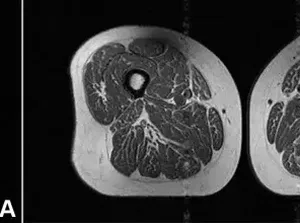

Studi MRI menunjukkan dampak buruk makanan ultra-proses pada lemak otot, meningkatkan risiko obesitas, diabetes, dan osteoarthritis.